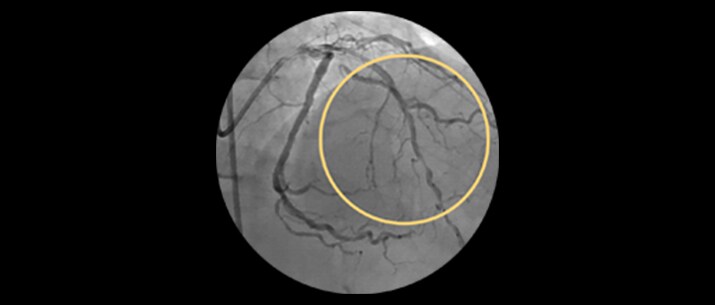

Approximately 20% of the coronary lesions treated today are long and diffuse.1,2

– Diffuse CAD may be underestimated by evaluation with coronary angiography.

– Determining reference vessel sizing can be challenging when the vessel is diffusely diseased.